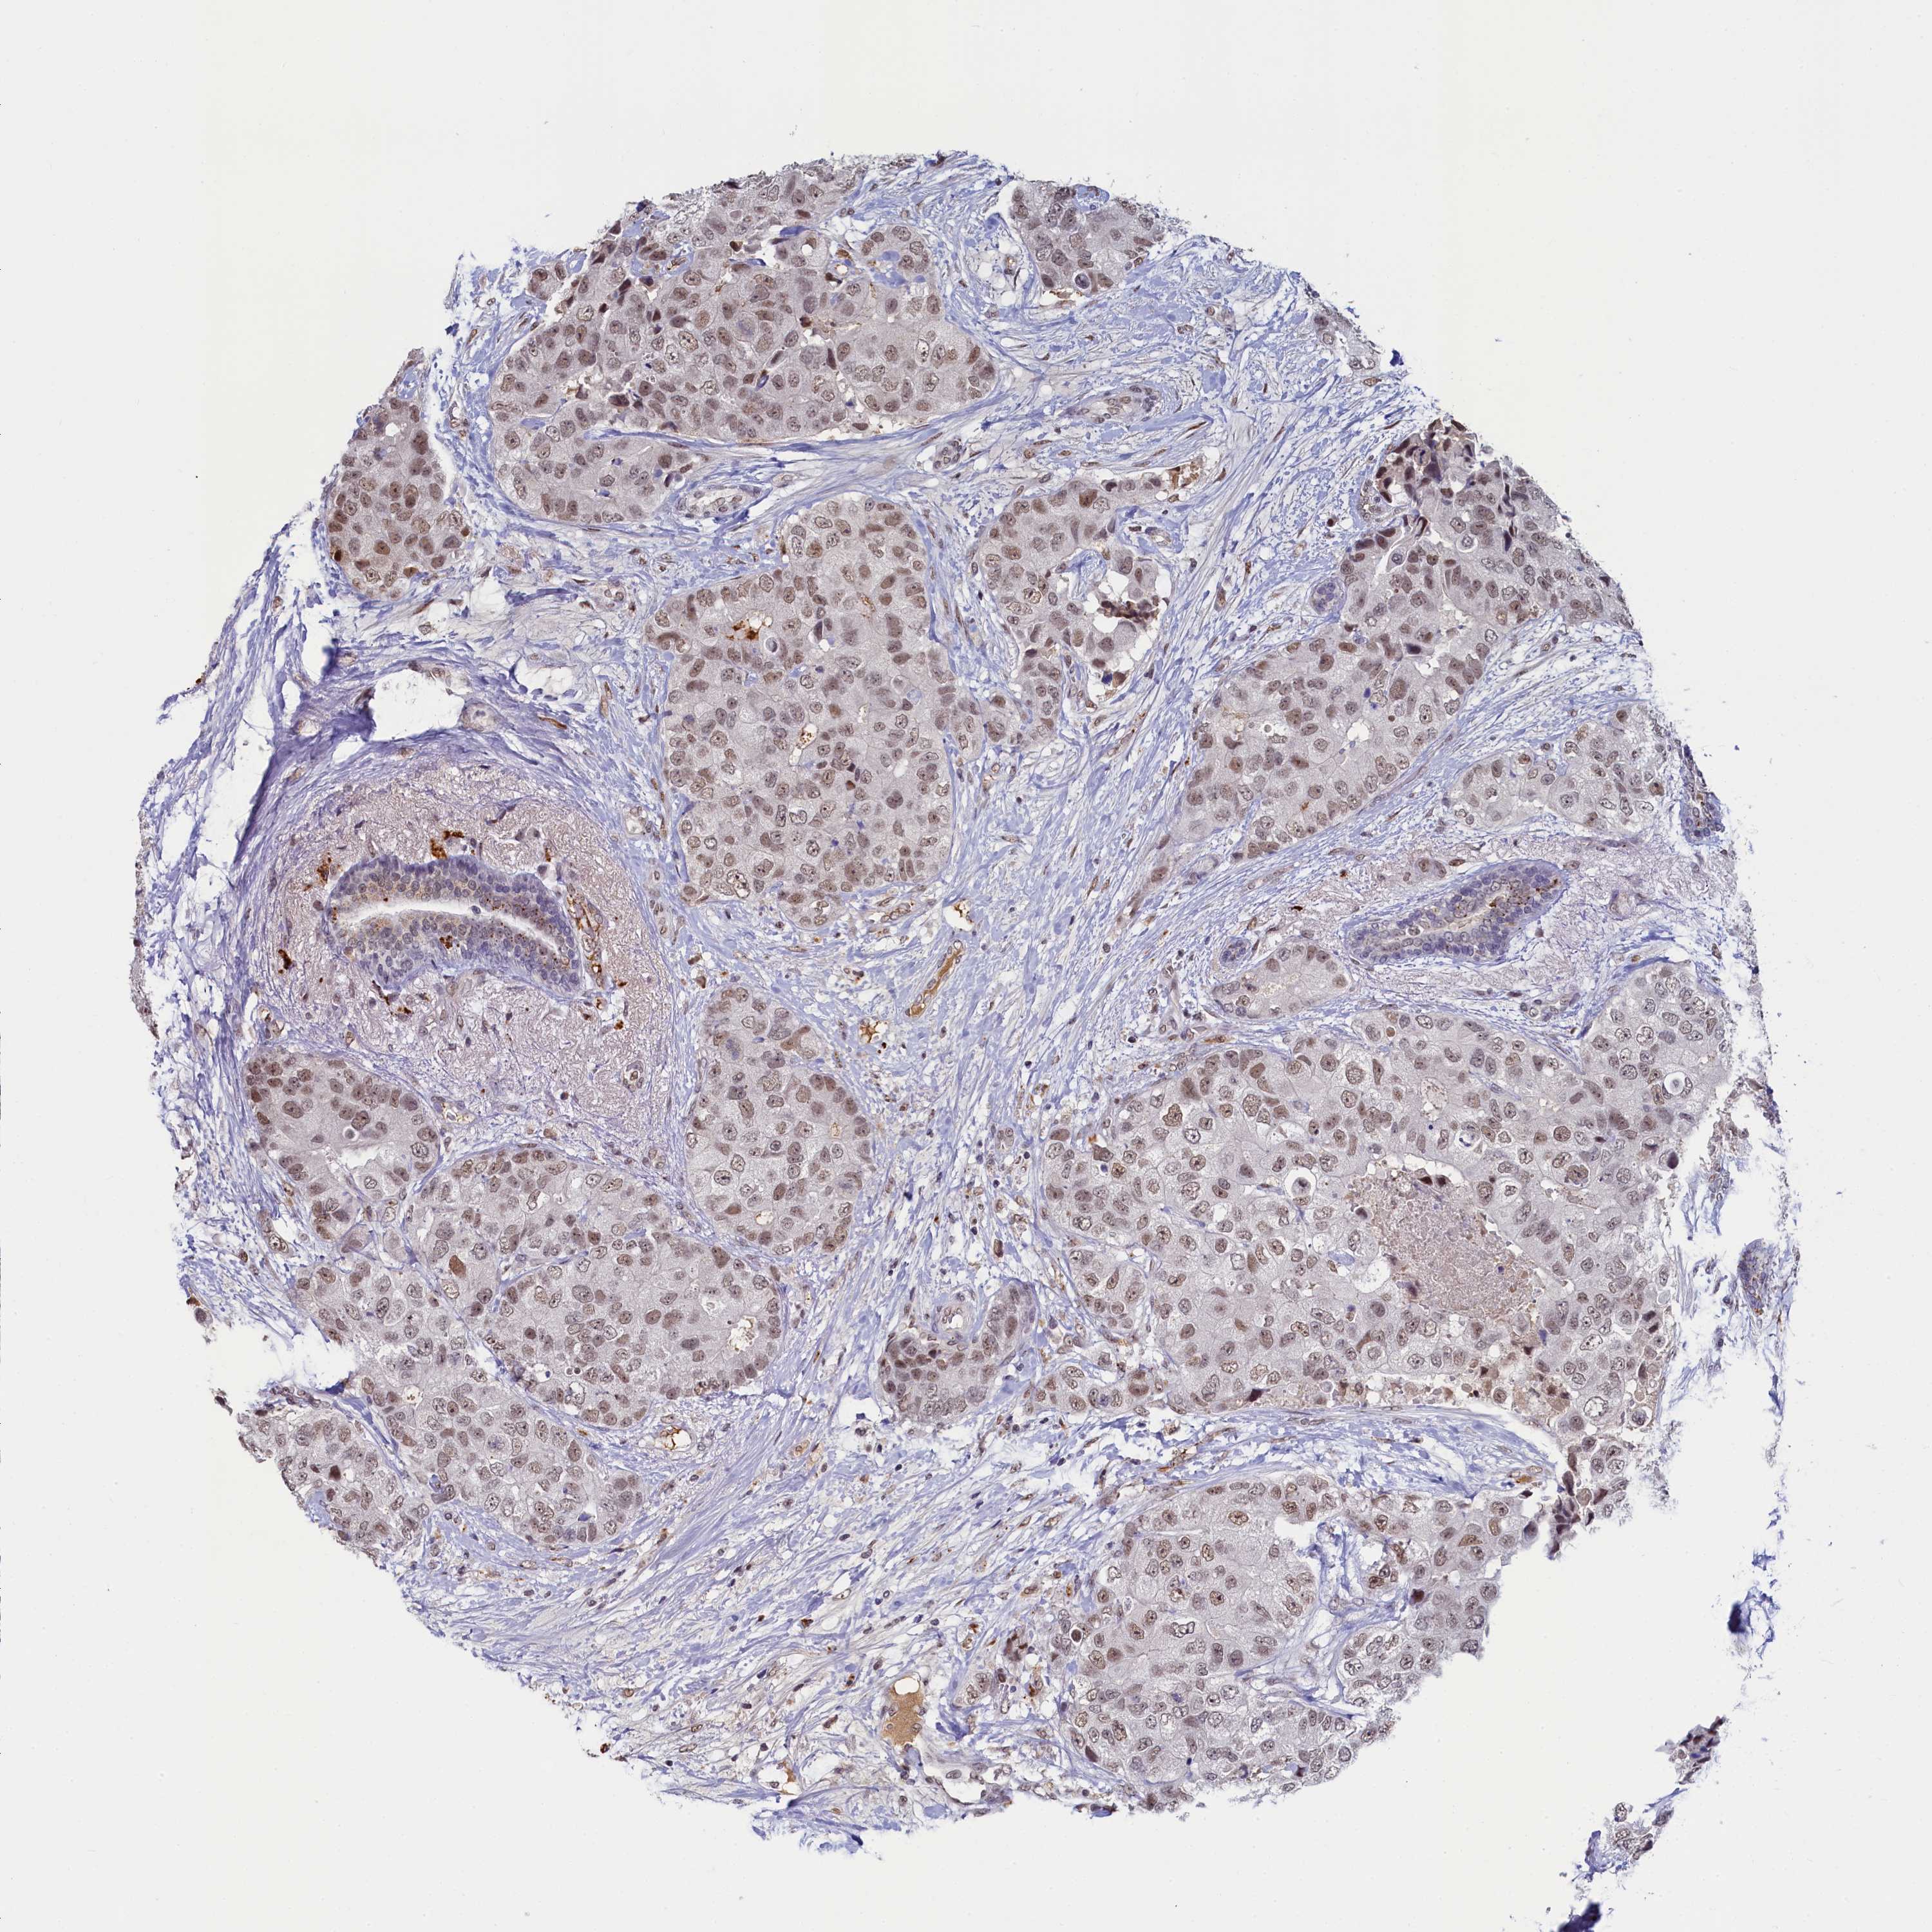

CANCER BREAST CANCER Show tissue menu

BRCA TCGA BRCA VALIDATION PROTEIN EXPRESSION